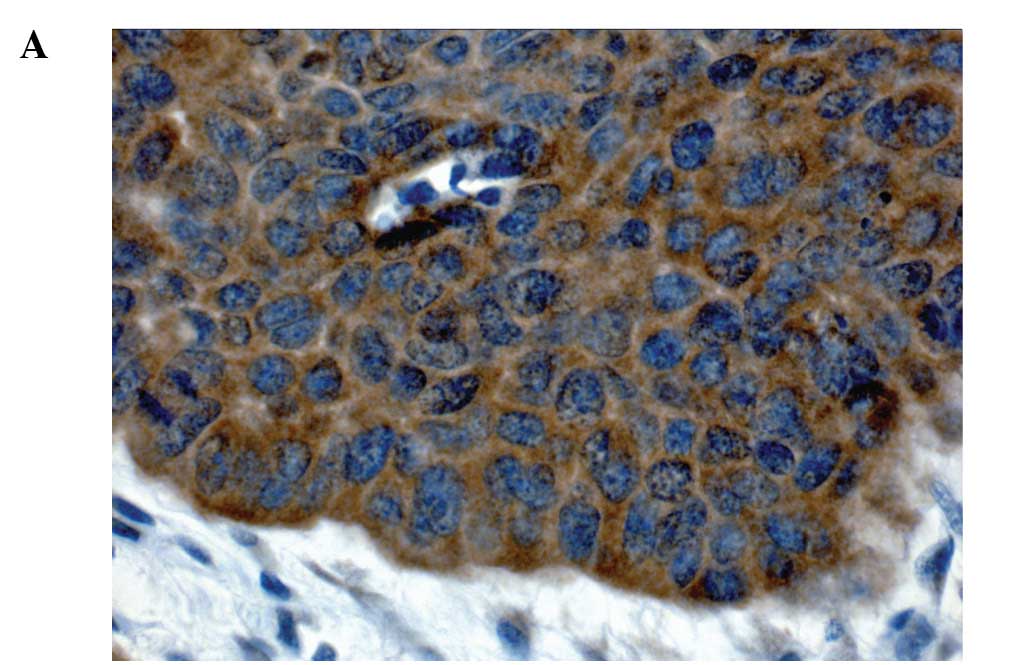

Prognostic value of c-Met expression in oral squamous cell carcinoma

Expression of c-Met, an oncogene encoding the receptor for the hepatocyte growth factor, was found to be associated with the progression of various types of human carcinomas including squamous cell carcinoma of the head and neck. This study was performed to analyze the prognostic role of c-Met in oral squamous cell carcinoma (OSCC) by detecting its expression in relation to clinicopathological features. Two hundred and eleven patients with OSCC were analyzed for c-Met expression by immunohistochemistry. Specimens with ≥50% of cancer cells showing staining for c-Met were considered c-Met-positive. A pairwise multiple-comparison procedure (Fisher's exact test) and survival analyses using the Kaplan-Meier method were used to analyze the data. One hundred and seventy-five patients (82.9%) showed positivity for c-Met, while 36 patients (17.1%) showed no immunopositivity. In contrast to published studies, there was no statistically significant correlation between c-Met expression and tumor size, lymph node status, distant metastasis or survival rates. However, a statistically significant negative correlation between c-Met expression and tumor stage was apparent (p=0.022). Hence, this study did not confirm the role of c-Met as a prognostic marker in patients with OSCC.

Figure 1

Figure 2